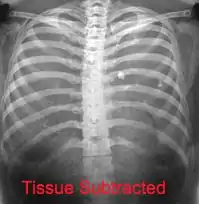

Les informations provenant des différentes structures traversées par le faisceau de rayonnements sont projetées sur un même plan pour former l'image. Par conséquent, il est souvent nécessaire de réaliser deux projections, à différentes incidences, pour pouvoir localiser une structure dans les trois dimensions de l'espace. Par exemple, en médecine, il s'agit fréquemment d'incidences de face et de profil. La loi d'atténuation des photons explique l'atténuation différentielle du faisceau à travers différentes structures, ce qui est à l'origine du contraste radiographique.

L'objet à radiographier, placé entre les positions et , à distance de la source pour que l'on puisse considérer qu'il est soumis à faisceau homogène de photons X ou gamma. Au fur et à mesure que le faisceau de photons traverse l'objet, il est atténué en fonction de l'épaisseur traversée et du coefficient d'atténuation . Ce coefficient d'atténuation dépend de l'énergie du photon et du numéro atomique Z de la structure rencontrée à la profondeur . L'organisme humain possède des tissus comme les os, très opaques aux photons, possédant donc un coefficient d'atténuation très élevé. Cela vient du fait que le tissu osseux est composé d'éléments de numéro atomique élevé comme le calcium. Le corps est aussi composé de tissus mous, peu opaques aux rayons X. Parmi eux, on différencie les organes de densité hydrique car composés essentiellement d'eau (muscles, foie) des densités graisseuses dont le coefficient d'atténuation est légèrement plus faible. Enfin, le poumon étant essentiellement composé d'air, il est qualifié d'organe de densité aérique. En effet le tissu pulmonaire, comme l'air, laisse passer la quasi-totalité des rayonnements. À la sortie du patient, le faisceau de photons n'est plus homogène mais est caractéristique des tissus traversés, on parle d'image radiante . Ces photons interagissent avec le détecteur, y déposant une énergie représentative des tissus traversés. Selon le mode de fonctionnement du détecteur, cette énergie sera utilisée pour produire l'image. La forte différence de coefficient d'atténuation entre les os et les autres tissus, crée un fort contraste de l'image, ce qui fait des rayons X un excellent outil d'imagerie osseuse. Pour obtenir une image d'organes n'ayant pas une densité spécifique, il est possible d'apporter in situ un produit de contraste de forte densité. C'est le cas pour l'imagerie des vaisseaux (injection intraveineuse d'iode), pour l'imagerie du système digestif (ingestion ou injection de baryte, à base de baryum), pour l'imagerie des articulations, ou arthroscopie (injection intra-articulaire d'iode) ou encore par exemple pour l'imagerie du système de reproduction de la femme, ou hystéroscopie (injection d'iode).

Le contraste de l'image radiante dépend du coefficient d'atténuation, l'épaisseur des structures rencontrées et de l'énergie des photons incidents. Les photons sont d'autant plus pénétrants qu'ils sont de forte énergie. Une augmentation du kilovoltage rend donc les photons plus pénétrants vis-à-vis de toutes les structures traversées, ce qui a pour effet de réduire le contraste[9]. Une augmentation du kilovoltage à mAs fixes augmente la dose reçue au patient et la quantité de photons reçue par le détecteur. Mais accompagnée d'une diminution des mAs, une augmentation du kilovoltage permet de réduire la dose au patient tout en conservant la même quantité de signal au niveau du détecteur. Seul le contraste est affecté par cette optimisation de radioprotection. Le contraste est aussi détérioré par la présence de rayonnement diffusé. Minimiser la proportion de rayonnement diffusé est possible en réduisant le volume diffusant (en limitant le champ irradié avec les diaphragmes ou en limitant l'épaisseur traversée par compression), en utilisant une grille antidiffusante ou avec la technique air-gap[10]. Le contraste final de l'image dépend également de la courbe sensitométrique du détecteur.